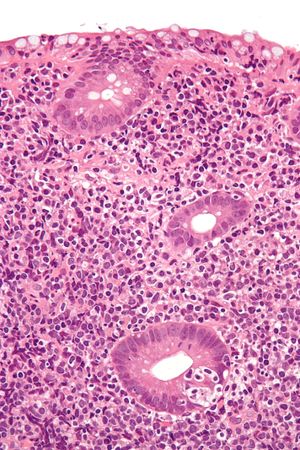

MALT 림프종은 내시경 검사 및 생검을 통해 진단한다. 육안으로 보이는 병변뿐만 아니라 정상 조직에서도 생검을 시행하여 정확도를 높인다.[41] 조직학적으로는 변연부 확장, 악성 소림프세포의 판(sheet) 형성, 림프상피성 병변 등이 특징적이다.[42] 악성 세포는 성숙한 소림프구와 다르게 중심세포를 닮은 세포(centrocyte-like cells)나 변연부/단핵구양 B세포(marginal zone/monocytoid B cells) 형태로 나타나기도 하며, 형질세포와 유사하게 분화하는 경우도 잦다.[1]

림프 소포는 MALT 림프종 어디에나 존재하지만 소포가 급속히 증식하거나 신생물 세포로 덮이는 경우가 많아 잘 구분되지 않을 수 있다. 거대세포로 변한 B세포는 소세포 사이에 흩뿌려져 있는 경우가 많으며, 거대 B세포 림프종과의 감별진단을 고려해야 한다.[2] 종양 세포는 반응성 여포의 변연대에서 여포 간 영역에 걸쳐 증식하며, 상피 내로 침윤하여 림프 상피 병변을 형성한다. 종양 세포는 배 중심 세포 유사 세포(centrocyte-like cell, CCL), 단구양 B 세포(monocytoid B cell), 소형 림프구 및 소수의 면역모세포(immunoblast)와 배 중심 아세포(centroblast) 등 다채로운 종양 세포로 구성된다. 형질 세포로의 분화가 관찰될 수도 있다. 종양 세포가 반응성 여포의 배 중심에 이동하여 겉보기에 여포 림프종과 유사한 구조를 만들기도 한다.

MALT 림프종을 배경으로 미만성 거대 B 세포 림프종(DLBCL)이 발생할 수 있다. 면역모세포(immunoblast)와 배 중심 아세포(centroblast)가 산재성이 아닌 시트 형태로 나타나는 경우에는 DLBCL로 진단하고 배경에 MALT 림프종이 존재함을 기술한다.

면역 염색에서 특이적인 마커는 없지만, B 세포 마커(CD20, CD79a) 양성, CD5, CD10, CD23은 음성이다. 형질 세포 분화가 있는 사례에서는 면역글로불린 경쇄 제한을 보인다.